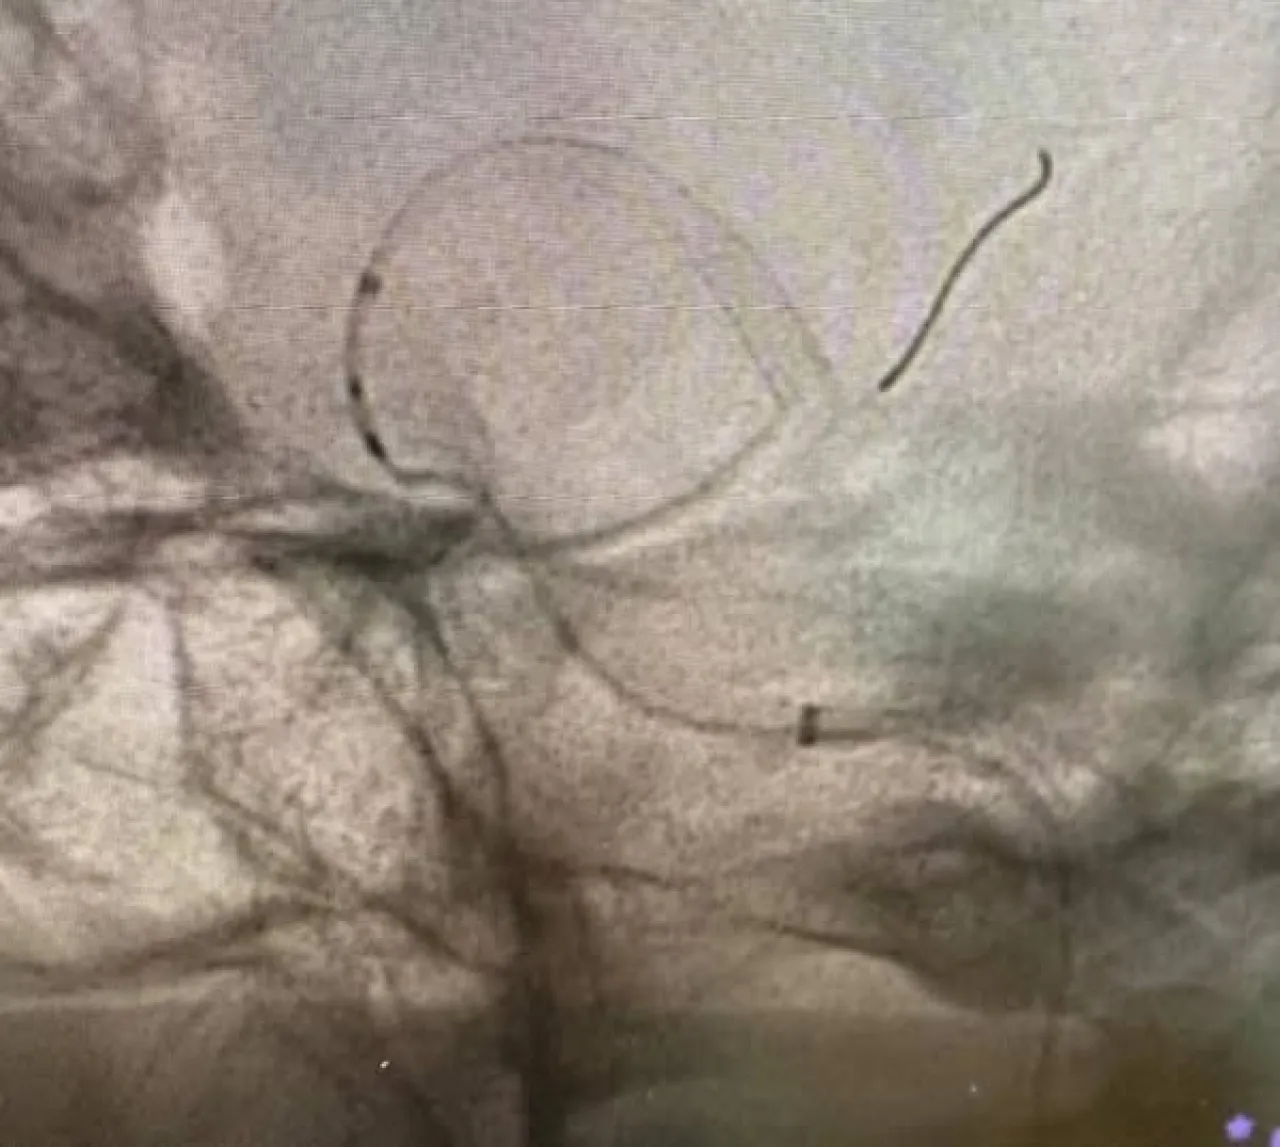

وخلال العملية، تم تركيب شبكة دقيقة بين الشريان الدماغي الأوسط والشريان السباتي الداخلي، ما ساعد على تحويل مسار الدم بعيدًا عن الكيس الدموي المنفجر، وبالتالي وقف النزيف بشكل كامل .

وأوضح الأستاذ الدكتور موفق الحيص أن هذه العملية تُعد من العمليات المعقدة والدقيقة جدًا، وتتطلب مهارة عالية في التعامل مع الأوعية الدموية الدماغية، مشيرًا إلى أن المستشفى يمتلك كوادر طبية مؤهلة وأجهزة متطورة تمكّنه من إجراء مثل هذه التدخلات العصبية الدقيقة .